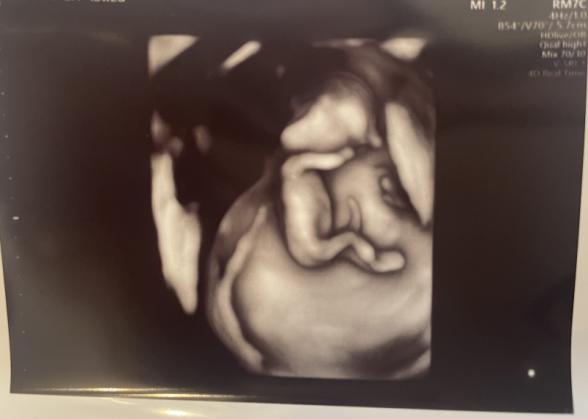

12週2日の時点で検診を受けた際のエコー写真で、胎児の頭の形が凹んでいるように見えて気になっています。

またエコー写真で後頭部〜首の後ろに暗い部分(=むくみ)があるとダウン症の傾向があるとネットで見てから、自分のエコー写真がそうではないか?と更に不安になってしまいました。

検診時に頭が凹んでいることを聞けず、先生からはエコーについて特に何も言われなかったです。ただ、その場でNIPTを検討していることを先生と会話したのでもしその傾向があれば指摘されてるはずだとは思いつつ、やはり不安になりこちらで相談させていただきました。

3D,4Dエコーの場合には、お子さんを立体的に映して見るものなので、超音波の当たる向きや位置などによって、影になる部分が出てきます。そのために穴が空いているように見えたり、影になっているところが凹んで見えたりするのかもしれませんね。ですが、医師から何も指摘がなかったということであれば、ご心配はないように思いますよ。何か異常があれば、医師は必ずママさんにお話しすると思いますし、特に問題の指摘がなければ、安心していただいて大丈夫だと思いますよ。